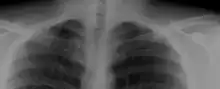

A cervical rib in humans is an extra rib which arises from the seventh cervical vertebra. Their presence is a congenital abnormality located above the normal first rib. A cervical rib is estimated to occur in 0.2%[6] to 0.5%[7] (1 in 200 to 500) of the population.[8] People may have a cervical rib on the right, left or both sides.[9][10]

Most cases of cervical ribs are not clinically relevant and do not have symptoms;[11][12] cervical ribs are generally discovered incidentally, most often during x-rays and CT scans.[7][8][10] However, they vary widely in size and shape,[7] and in rare cases, they may cause problems such as contributing to thoracic outlet syndrome,[11] because of pressure on the nerves that may be caused by the presence of the rib.[11][13]

On imaging, cervical ribs can be distinguished because their transverse processes are directed inferolaterally, whereas those of the adjacent thoracic spine are directed anterolaterally.[15]